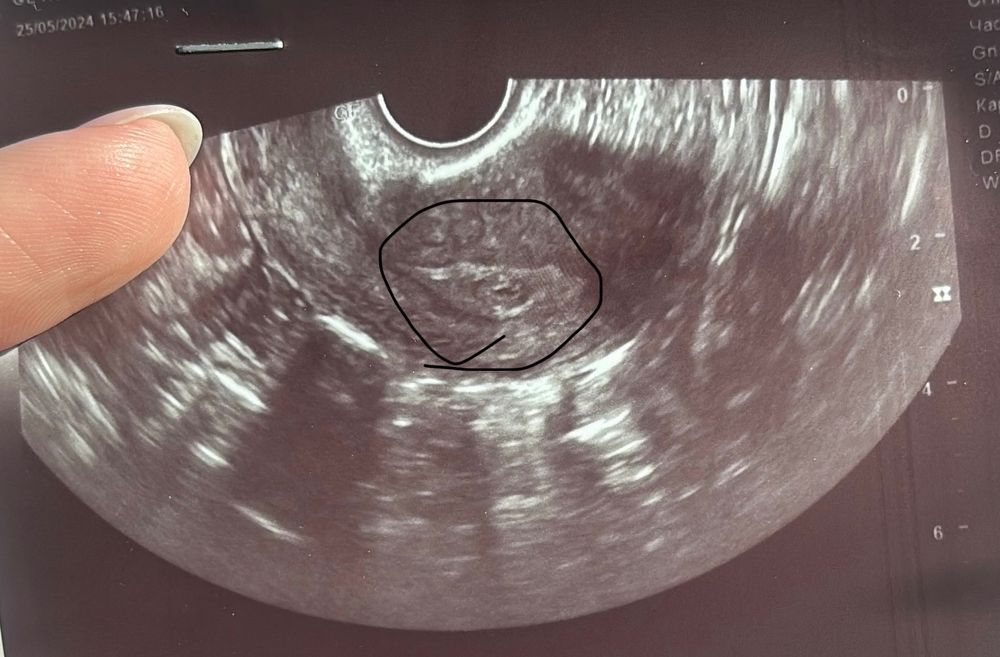

приезжаю в клинику ,делают мне узи (узист,даже не гинеколог)и говорит ,что в матке вроде что-то есть,но я не знаю что,желтое тело тоже очень плохое и не ясно желтое ли это тело,эндометрий 7,7 .Я в полной панике ,подскажите что да как?Хгч на 7дпп-104,9дпп-443,11дпп-1390

Рыбка, а почему тогда не увидели желтое тело?и как вы думаете ,на фото обвела в кружок ,это может все таки оно?

Елена, то, что Вы обвели в кружок на фото, это плодное яйцо в эндометрии. А жёлтое тело, вырабатывающее прогестерон, находится в яичнике. А когда делают например крио на згт, жёлтого тела вообще нет, и беременность развивается на прогестероновой поддержке (Утрожестан, Дюфастон). У Вас же есть поддержка? Не переживайте, она заменит жёлтое тело, если его действительно нет)